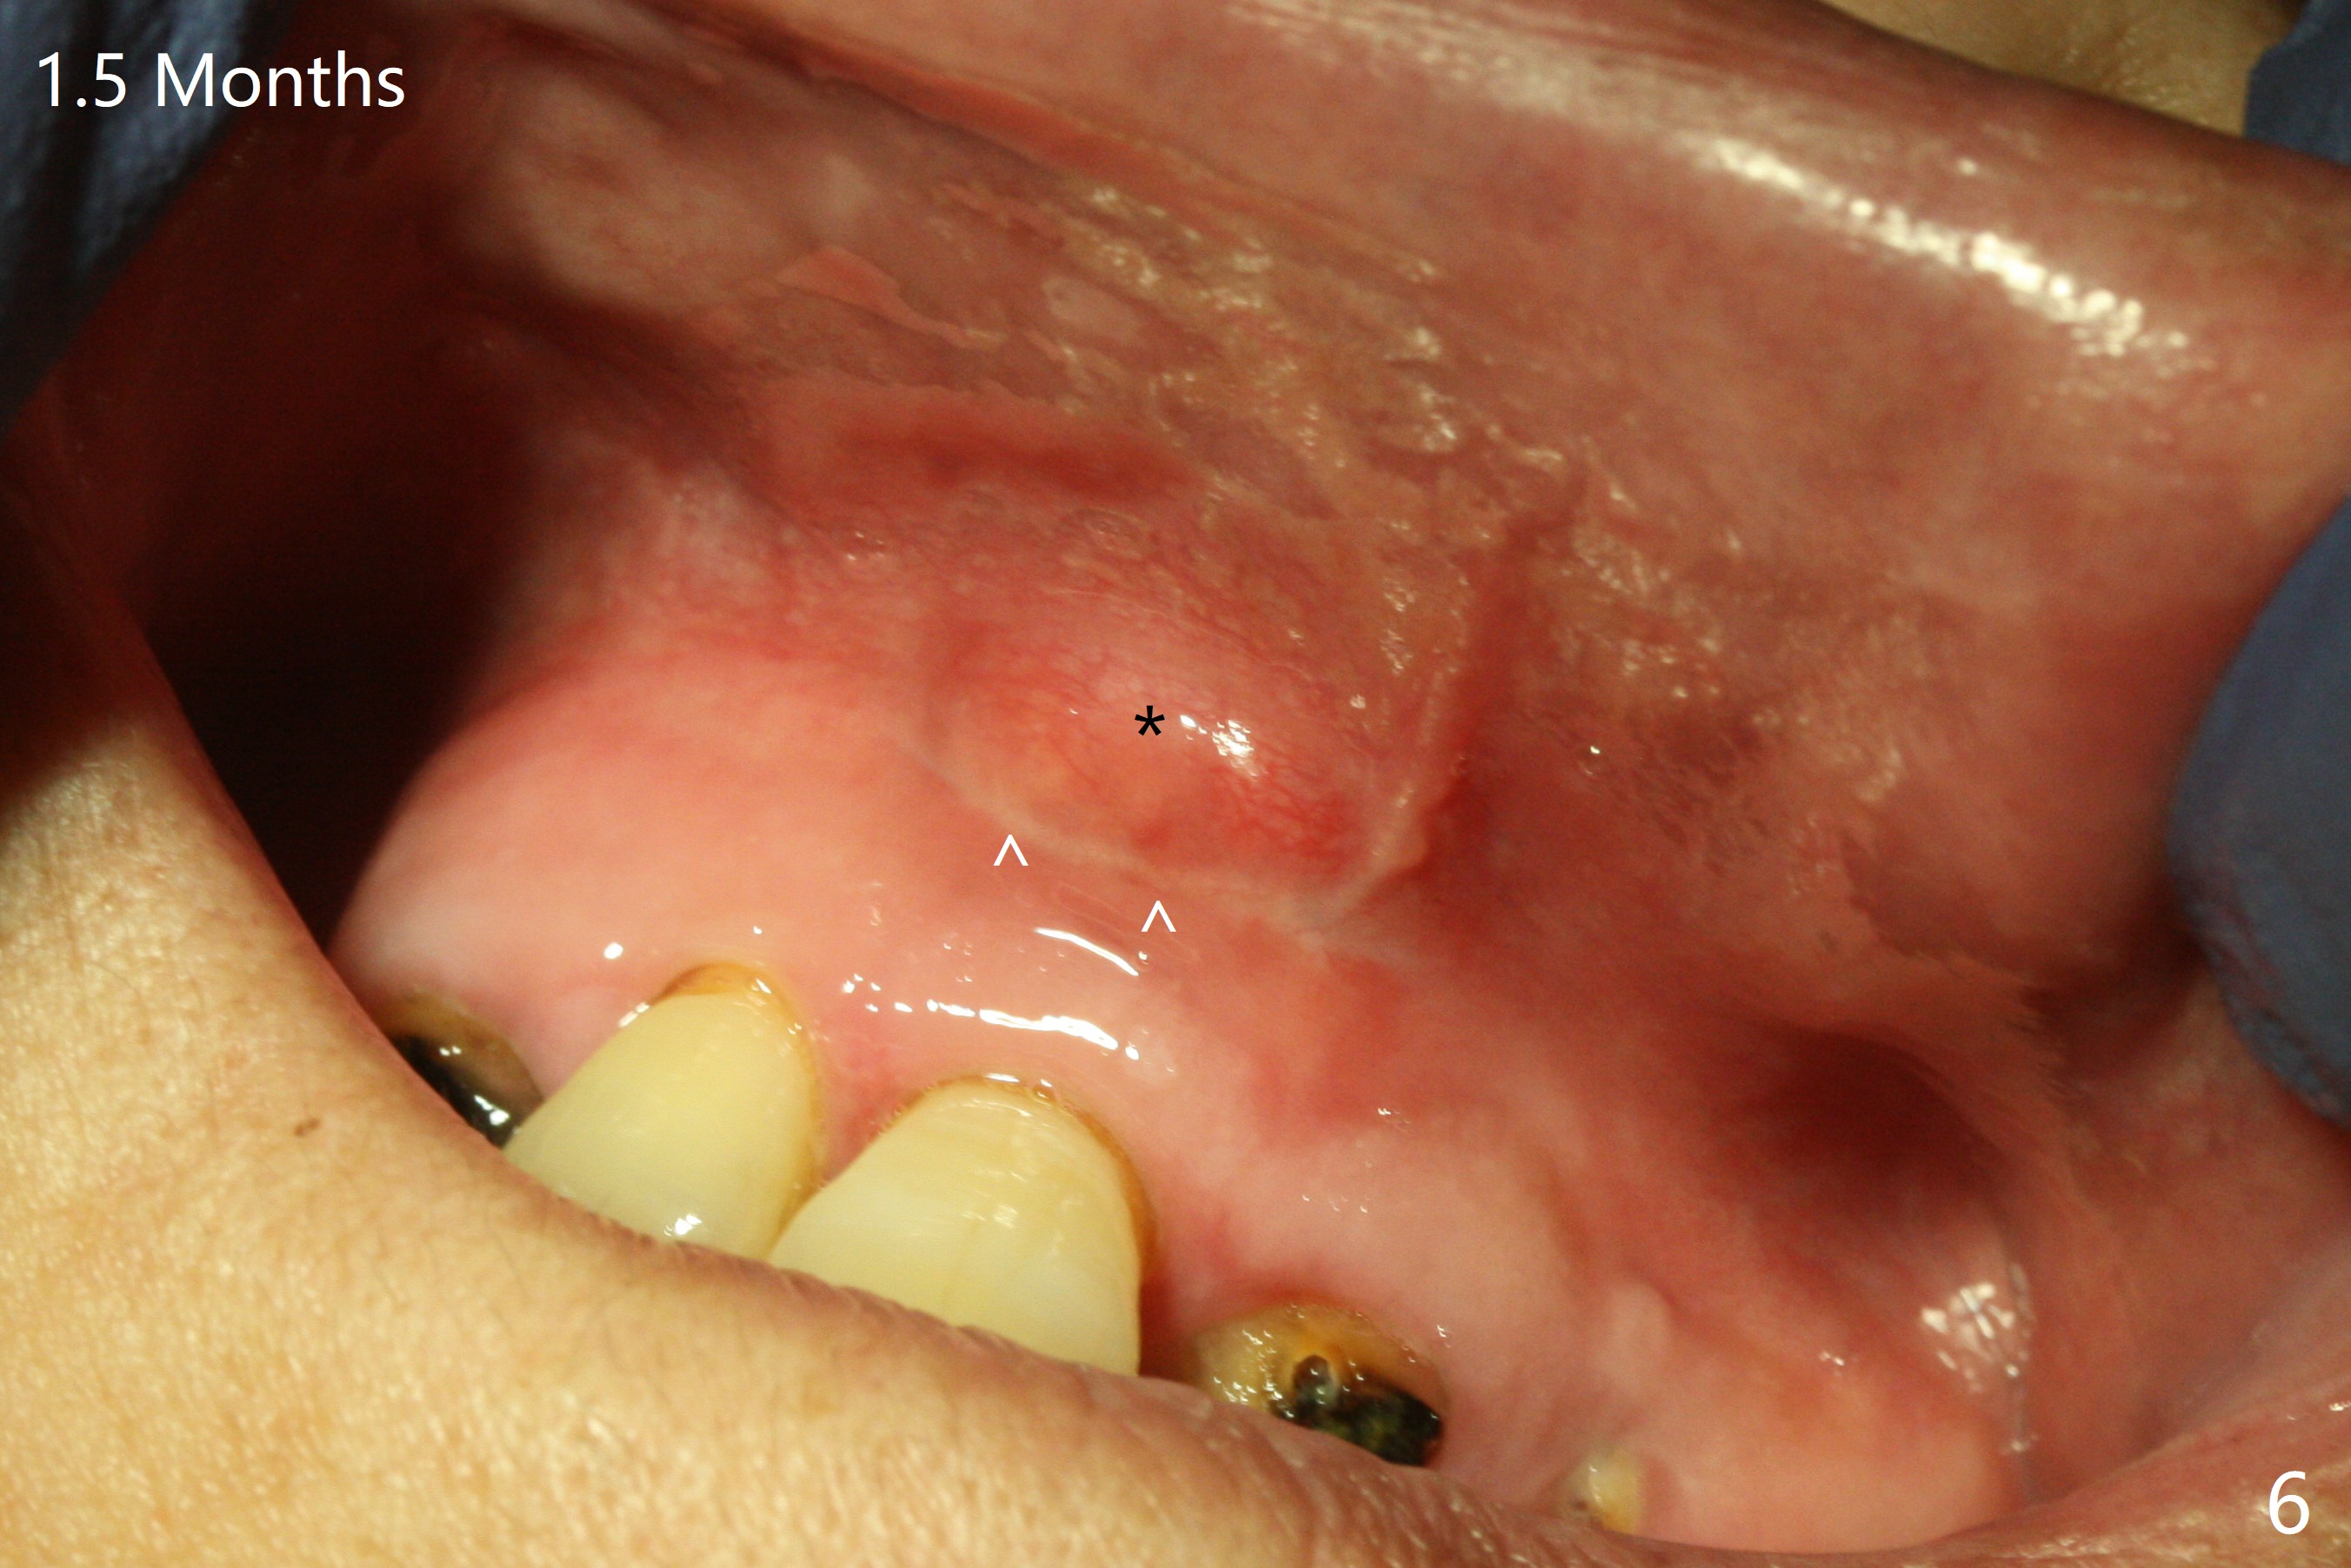

A 86-year-old woman with diabetes (under control with Insulin) and poor dentition (Fig.1) presented to clinic with an abscess apical to the tooth #8 (nonvital, Fig.2). CBCT (Fig.3) or PA (Fig.4) does not show radiolucency at #7 or 8. The incised abscess with purulent drained is superficial to the apparently intact periosteum (Fig.5 *). The patient is reluctant to have #7 and 8 extracted, since they are the only remaining functional dentition. The infection recurs 1.5 months later (Fig.6 * (^: previous incision)). With the periosteum elevated, fenetration over the apex of the tooth #7 (vital in pulpal test) is only seemingly significant finding (Fig.7). The abscess (Fig.8 A) is shown superficial to the periosteum (*). The infection is expected to relapse. What should be done otherwise? Full mouth extraction has been discussed.